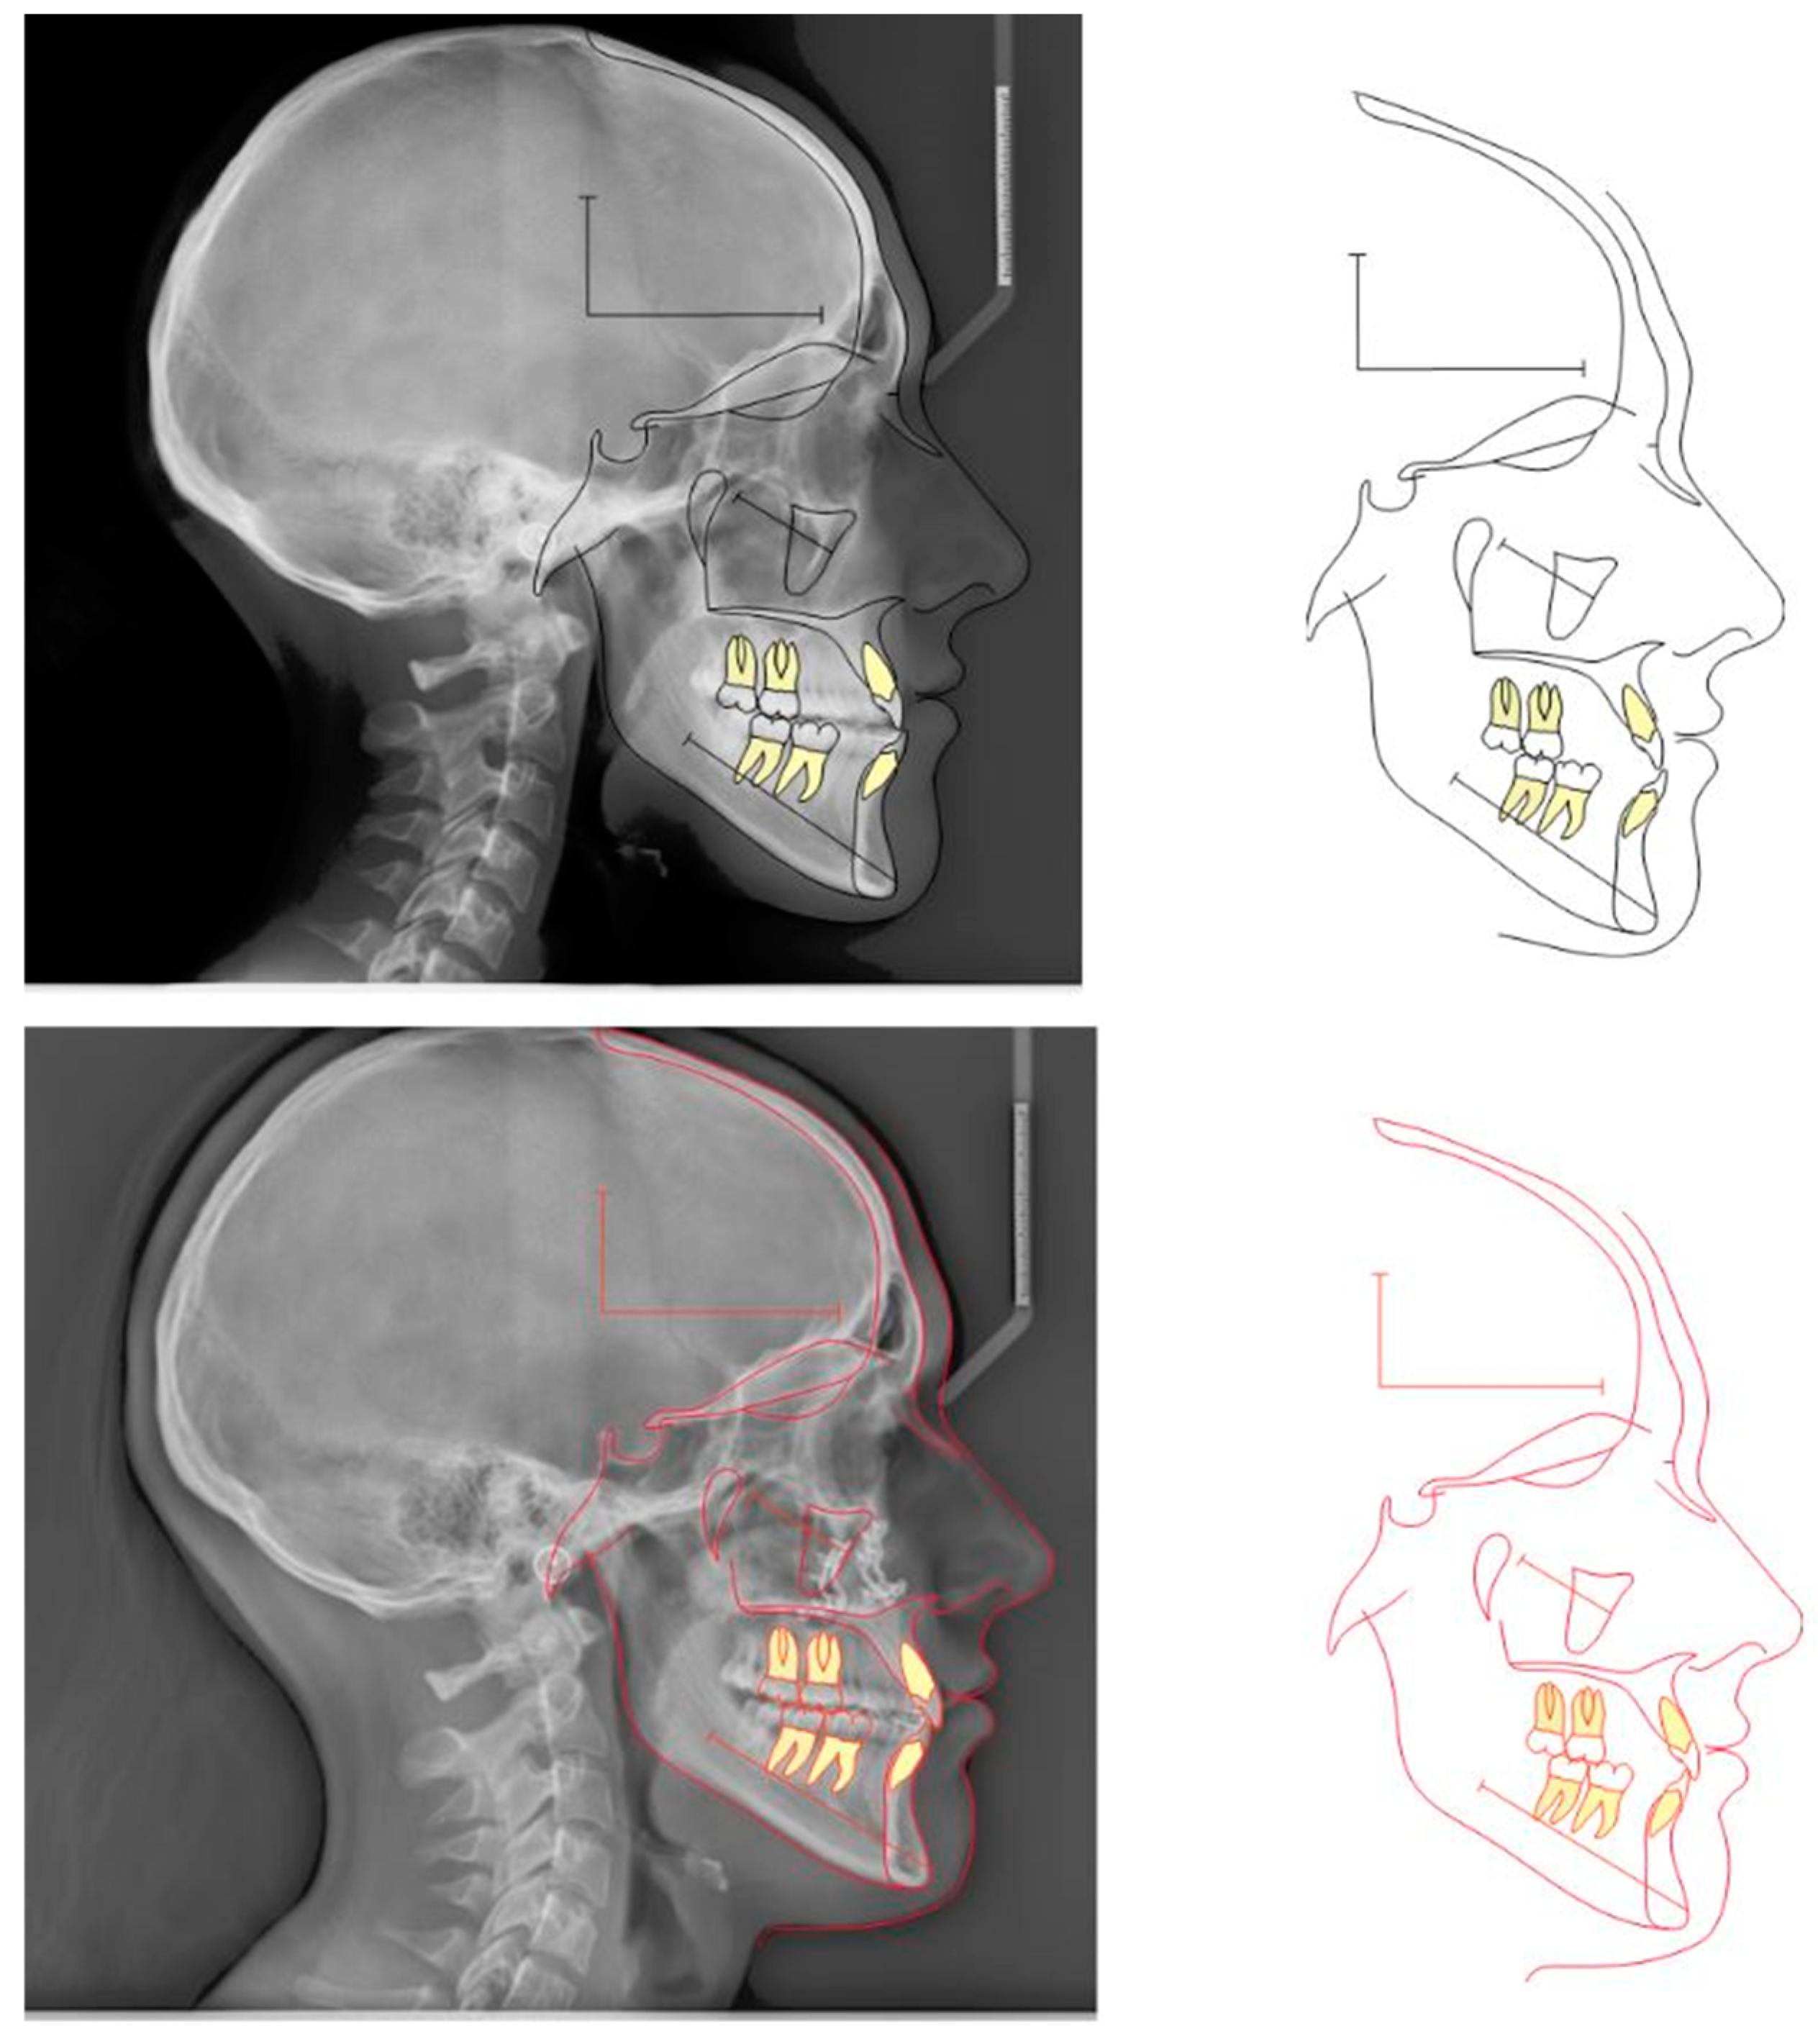

2.1. Diagnosis and Individual Treatment Planning

2.2. Clinical Preparations